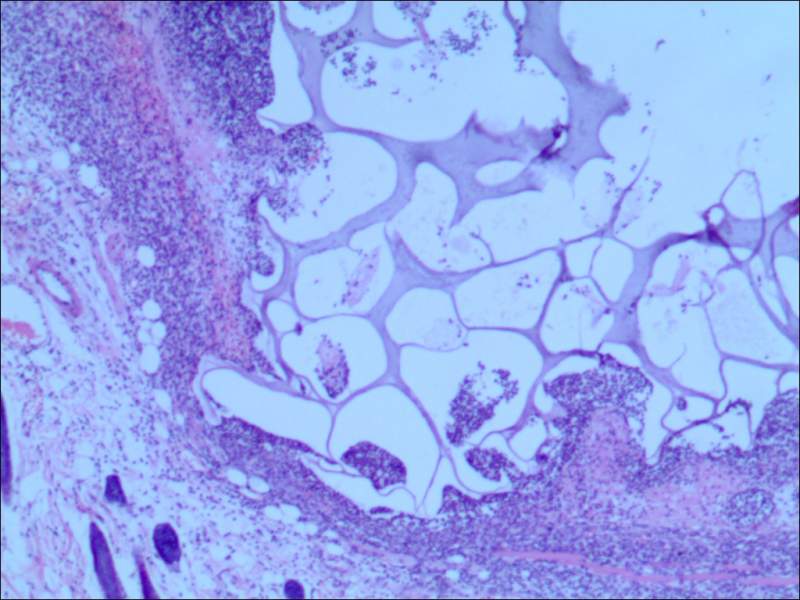

哪位大神帮我看一下这张HE染色的图片